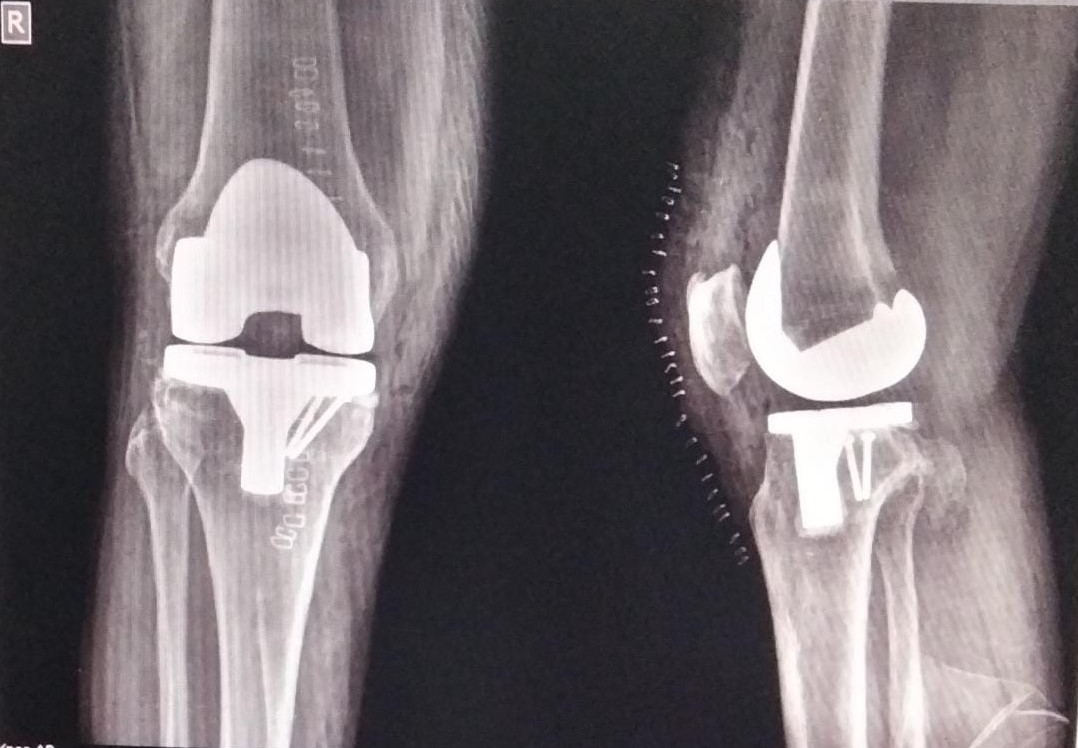

Knee and Hip Replacement